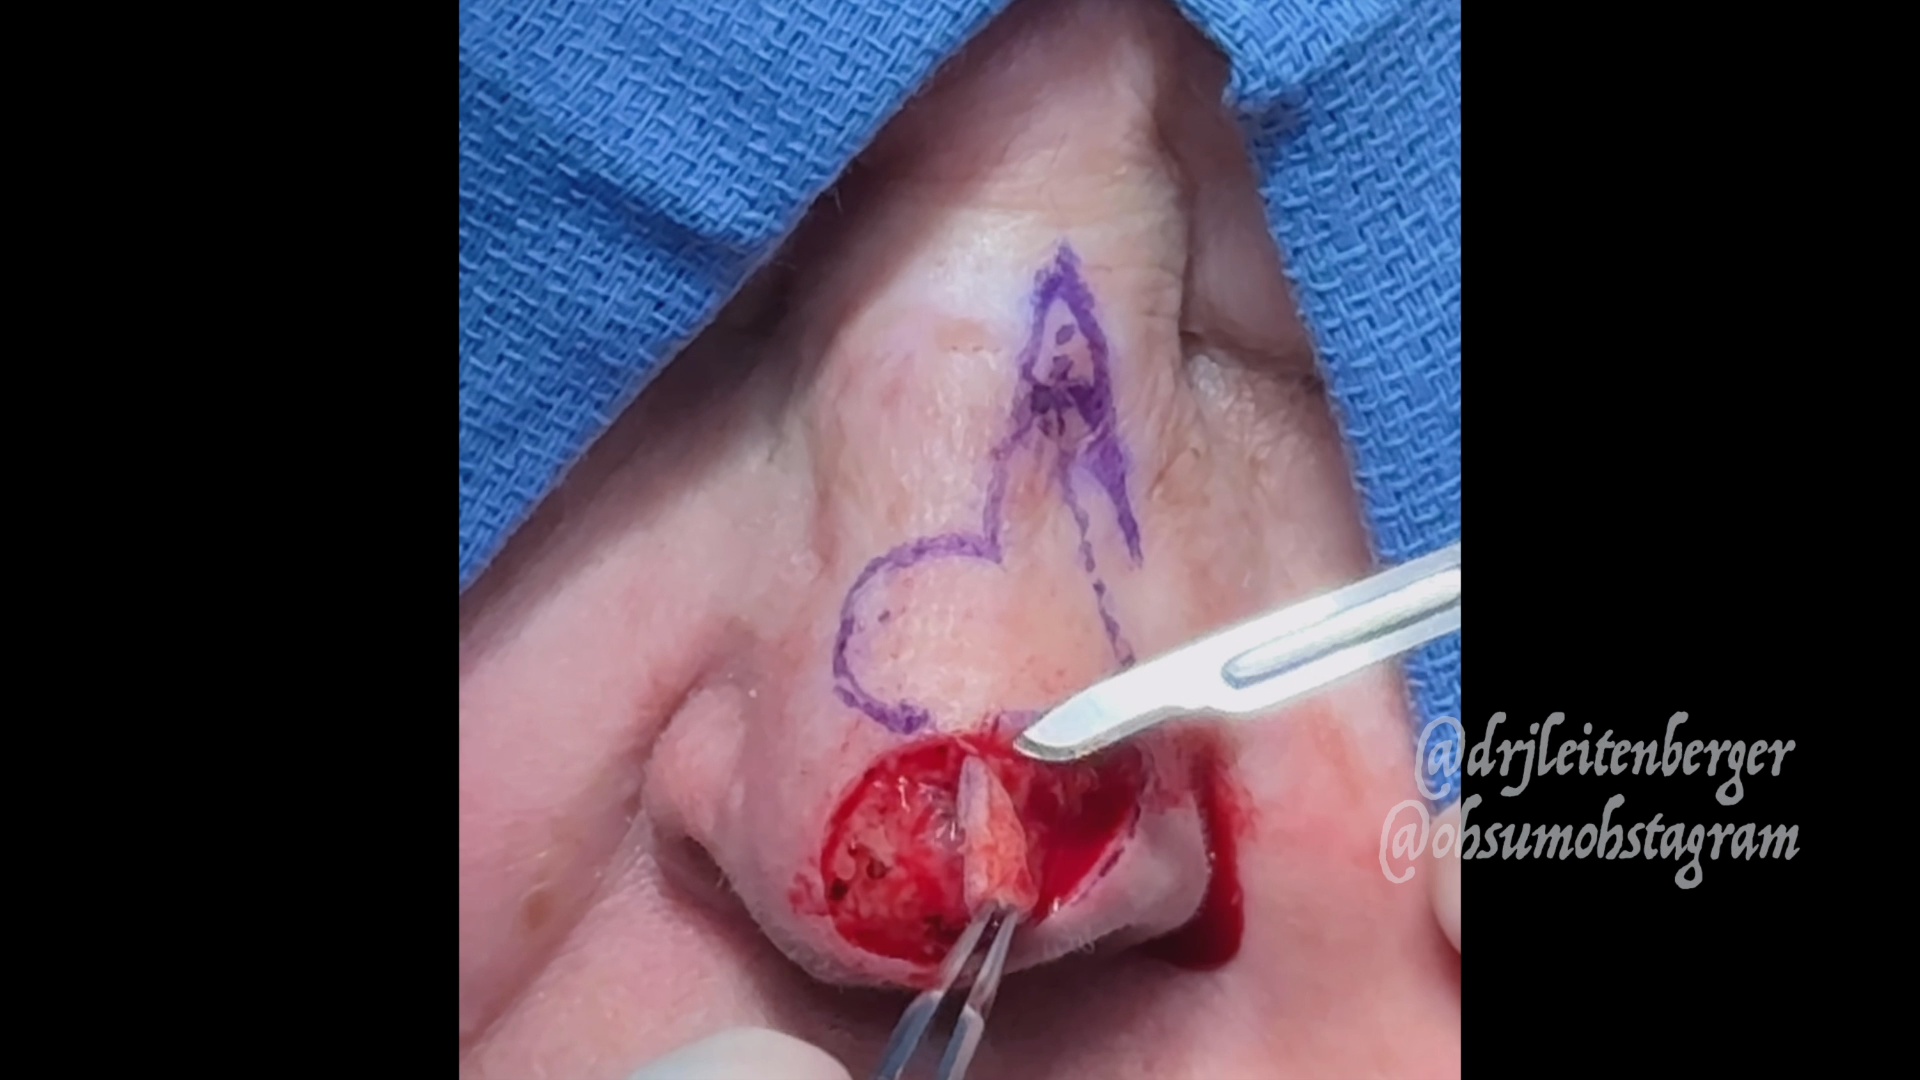

Watch the Full VideoA 3 yo girl was referred to the ENT clinic after her PCP noticed an abnormal TM on the left. She has a history of a 2 ear infections prior to presentation. She is asymptomatic, with no pain and no drainage from her TM. Her audiogram was normal. Her physical eventually revealed the presence of a relatively large keratin pearl on her TM, without obvious middle ear effusions. After a short period of observation the family decided to have it removed. The case was performed endoscopically in a trans-canal approach. The lesion was dissected mainly with a straight pick. The fibrous layer underneath was found to be intact and no myringoplasty was necessary. The patient was was seen again 2 months post-op and her TM was found to be normal with a normal audiogram.